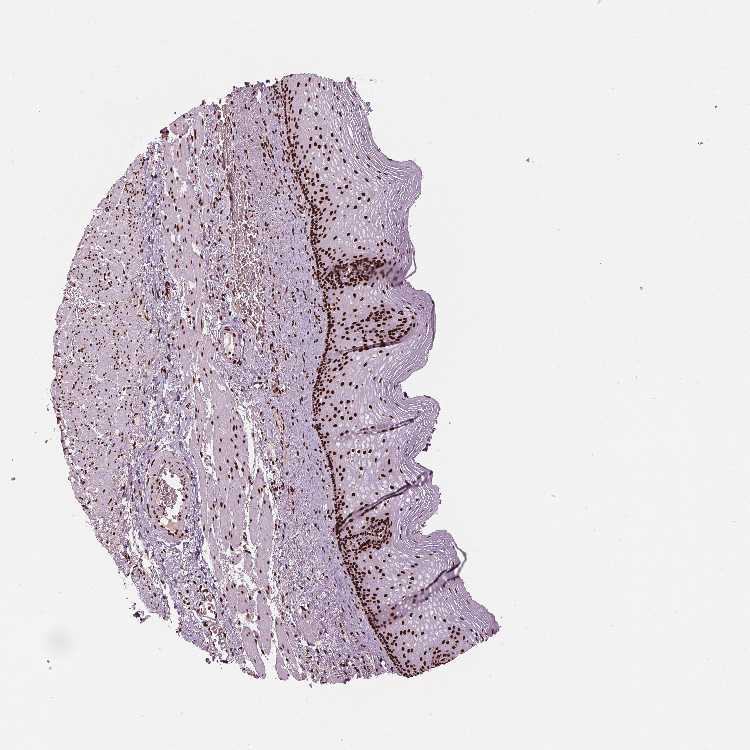

ESOPHAGUS - Antibody stainingi

Antibody staining in the annotated cell types in the current human tissue is reported as not detected, low, medium, or high, based on conventional immunohistochemistry profiling in selected tissues. This score is based on the combination of the staining intensity and fraction of stained cells.

Each image is clickable and will lead to virtual microscopy that enables deeper exploration of all samples and also displays staining intensity scores, fraction scores and subcellular localization as well as patient and tissue information for each sample.

Antibody HPA015055Antibody HPA061646Antibody CAB068177Antibody CAB068178

Squamous epithelial cells MediumHighMediumHigh